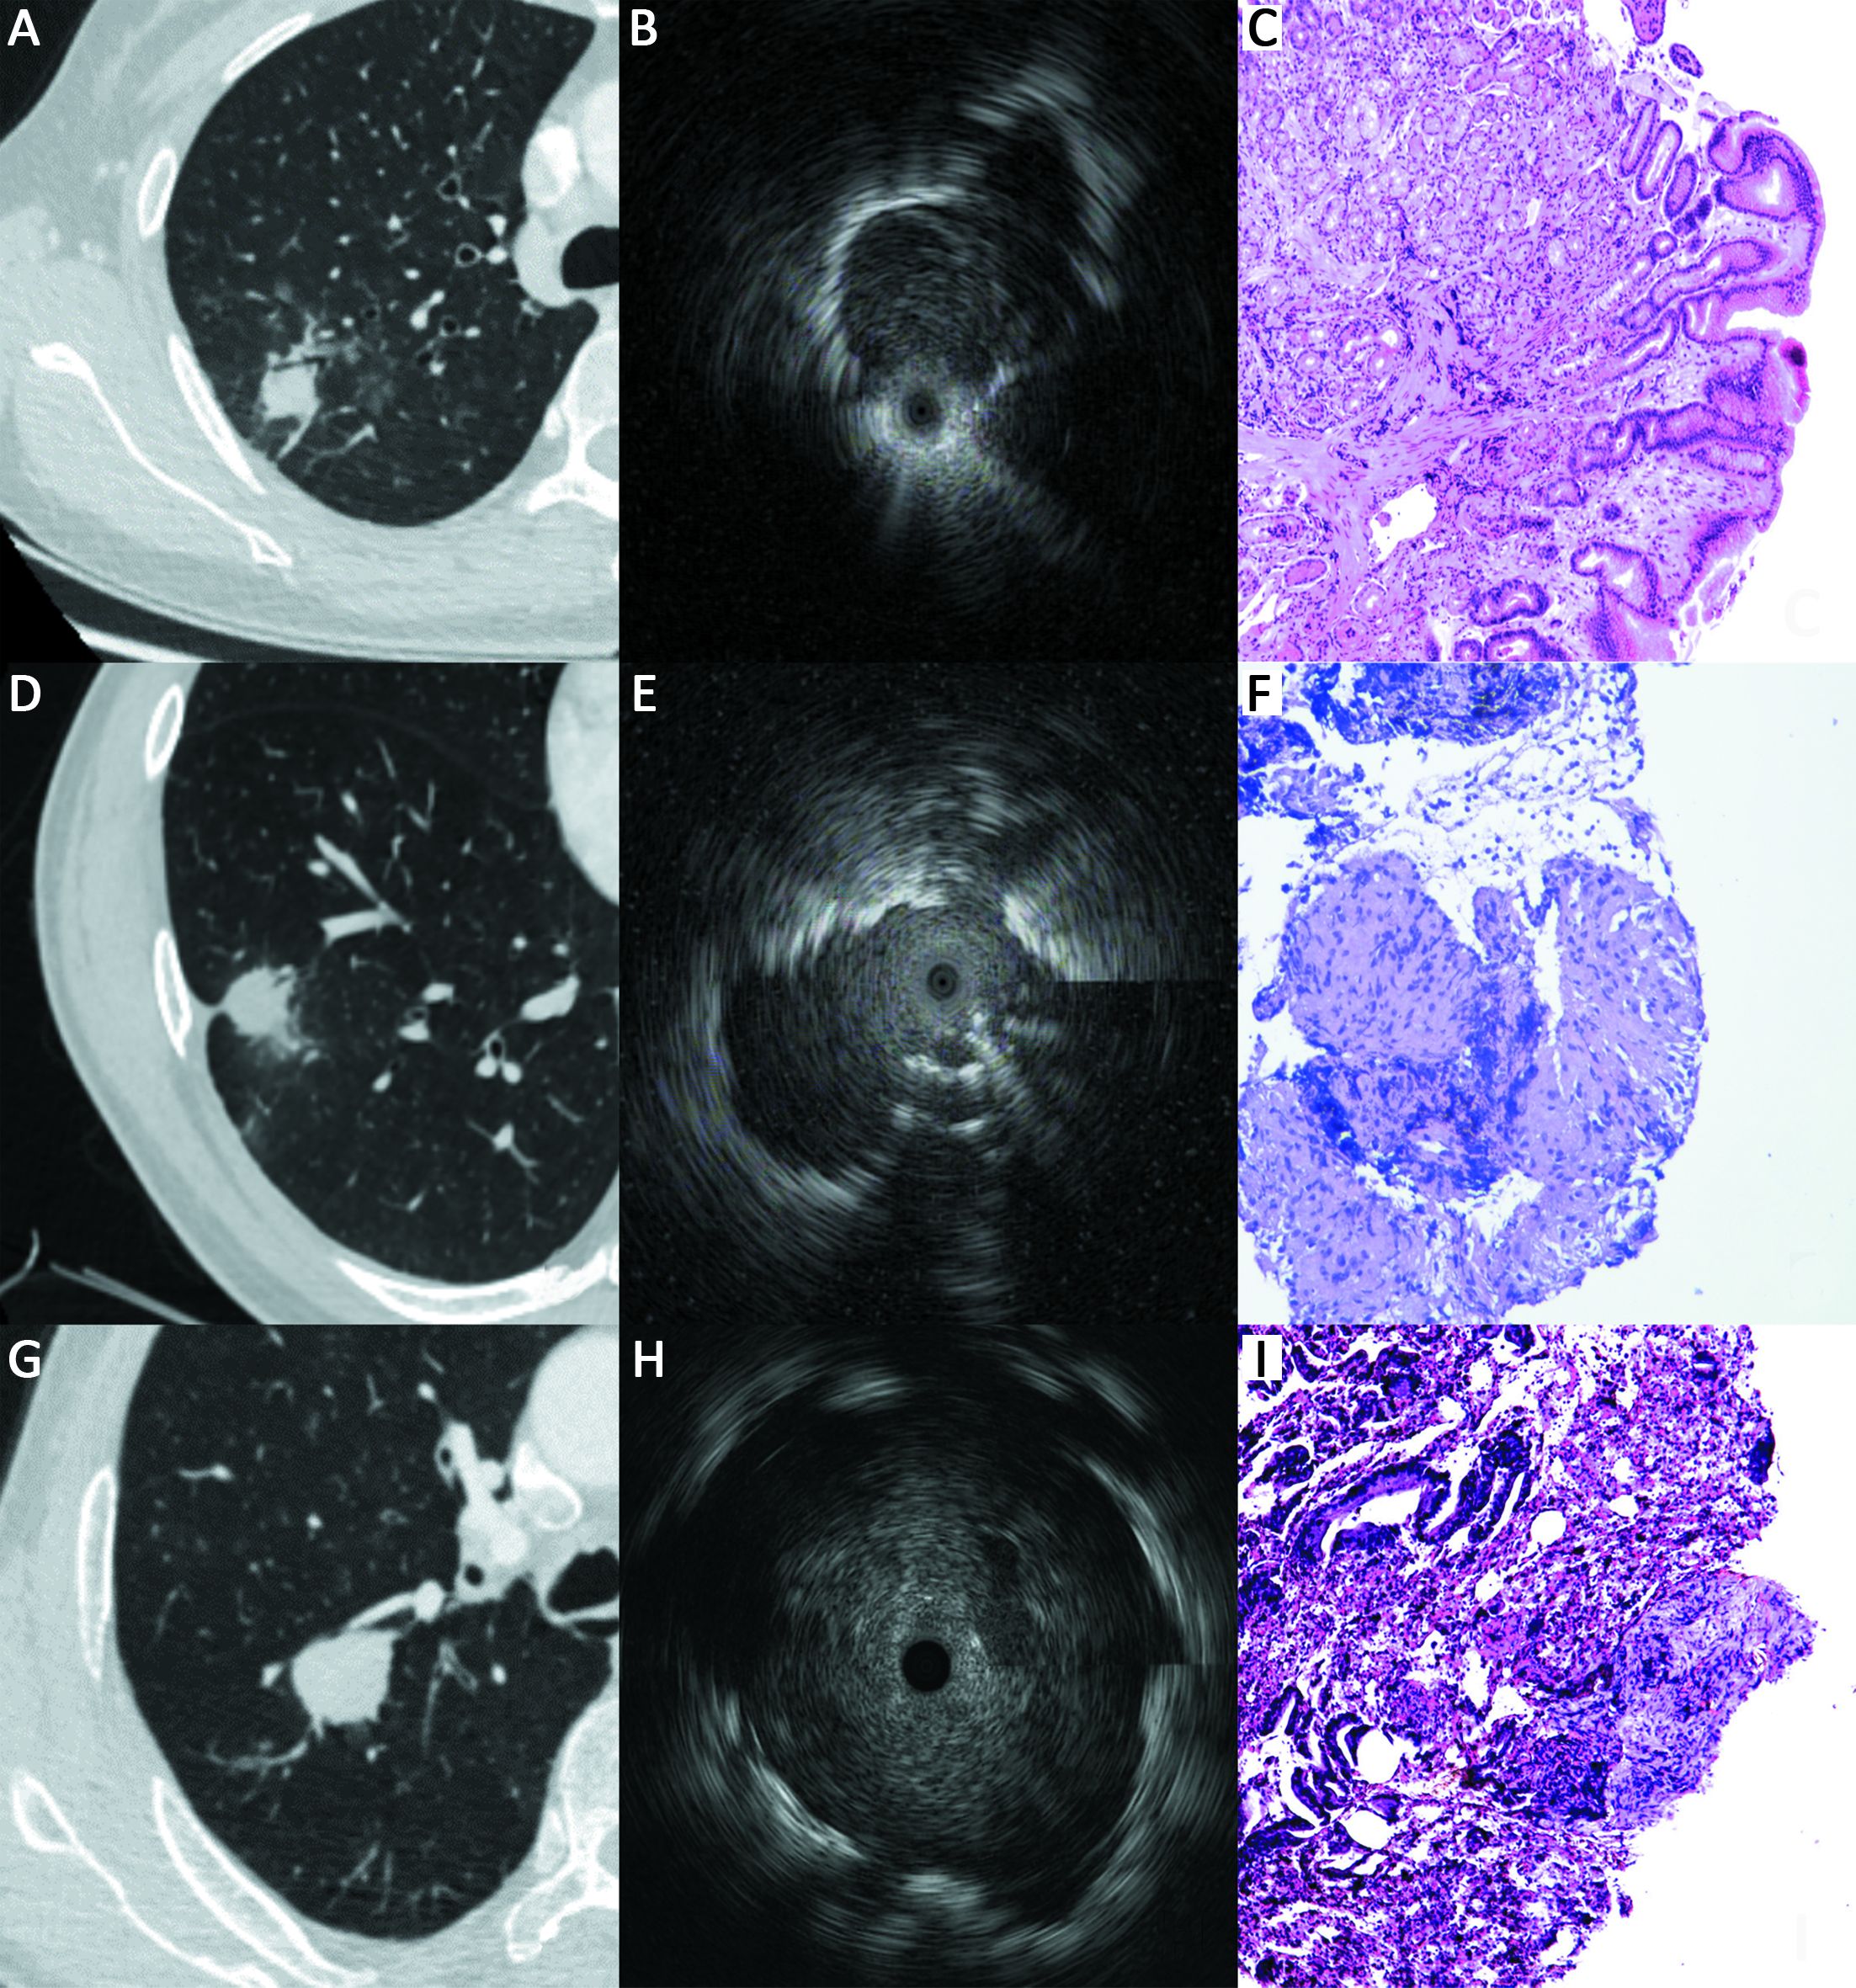

ObjectiveFluoroscopy guidance is generally required for endobronchial ultrasonography with guide sheath (EBUS-GS) in peripheral pulmonary lesions (PPLs). Virtual bronchoscopic navigation (VBN) can guide the bronchoscope by creating virtual images of the bronchial route to the lesion. The diagnostic yield and safety profiles of VBN without fluoroscopy for PPLs have not been evaluated in inexperienced pulmonologist performing EBUS-GS. MethodsBetween January 2016 and June 2017, consecutive patients with PPLs referred for EBUS-GS at a single cancer center were enrolled. The diagnostic yield as well as safety profiles was retrospectively analyzed, and our preliminary experience was shared. ResultsA total of 109 patients with 109 lesions were included, 99 (90.8%) lesions were visible on EBUS imaging. According to the procedure time needed to locate the lesion on EBUS, 24.8% (27/109) were deemed technically difficult procedures; however, no significant relationships were identified between candidate parameters and technically difficult procedures. The overall diagnosis yield was 74.3% (81/109), and the diagnostic yield of malignancy was 83.7% (77/92). Lesions larger than 20 mm [odds ratio (OR), 2.758; 95% confidence interval (95% CI), 1.077−7.062; P=0.034] and probe of within type (OR, 3.174; 95% CI, 1.151−8.757, P=0.026) were independent factors leading to a better diagnostic yield in multivariate analysis. About 30 practice procedures were needed to achieve a stable diagnostic yield, and the proportion of technically difficult procedures decreased and stabilized after 70 practice procedures. Regarding complications, one patient (0.9%) had intraoperative hemorrhage (100 mL) which was managed under endoscopy. ConclusionsVBN without fluoroscopy guidance is still useful and safe for PPLs diagnosis, especially for malignant diseases when performed by pulmonologist without previous experience of EBUS-GS. VBN may simplify the process of lesion positioning and further multi-center randomized studies are warranted.